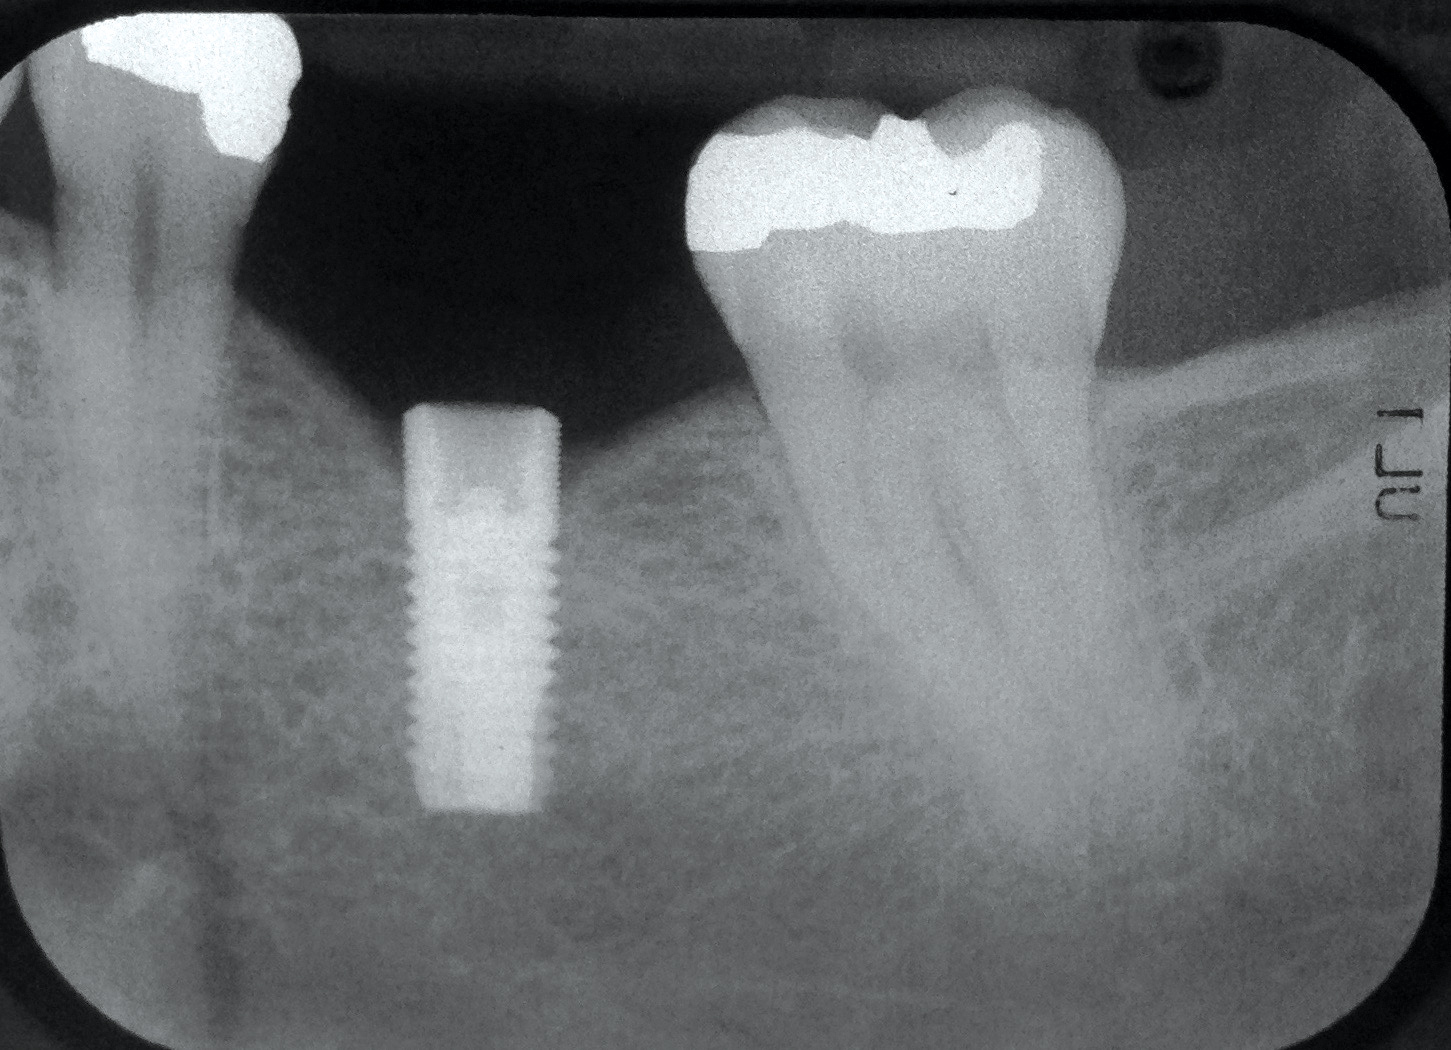

Fig 16. Radiograph depicting closed contact at time of implant insertion.

Fig 17. Open proximal contact between implant and adjacent tooth 3 years post insertion.